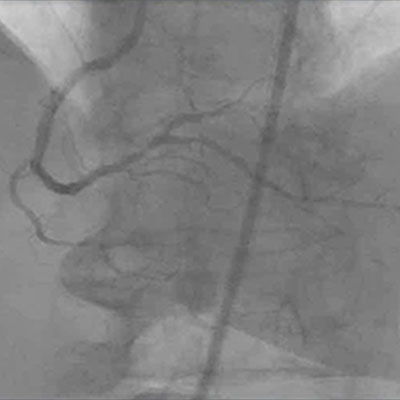

L’échographie intravasculaire est une méthode précise qui aide à déterminer : - Déploiement complet du stent - Apposition - Absence de dissection des extrémités ou autres complications après implantation

La mortalité intra-hospitalière, tout comme les réadmissions de 30 jours, est un indicateur important du programme d’achat Medicare axé sur la qualité qui influence les scores qualité hospitaliers et les refus de paiement de Medicare.10,11 Le guidage par échographie intravasculaire a été associé à une mortalité intra-hospitalière de 0,4 % tandis que le guidage par angiographie seule a été associé à une mortalité intra-hospitalière de 0,8 % (p < 0,001), soit une réduction de 50 %.5 le positionnement des stents à élution de médicaments guidé par échographie intravasculaire a vu réduire le taux de réadmissions de 30 jours.12,13

Le cathéter d’échographie intravasculaire numérique Eagle Eye Platinum est le choix numéro 1 des médecins pour l’imagerie échographique intravasculaire (aux États-Unis)*. En tant que cathéter d’imagerie échographique intravasculaire plug and play unique, il est conçu dans une optique de facilité d’utilisation et de productibilité optimale. Parmi ses caractéristiques figurent une pointe effilée souple, un revêtement hydrophile GlyDx pour un pouvoir lubrifiant accru, une longue lumière à échange rapide pour un pouvoir de poussée supérieur, trois marqueurs radio-opaques et la compatibilité avec SyncVision pour le recalage automatique avec l’angiographie.